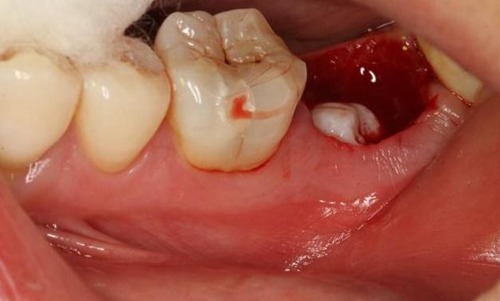

圖1.術(shù)前的CBCT檢查:37頰側(cè)部分牙根被完全壓迫吸收。

1.jpg